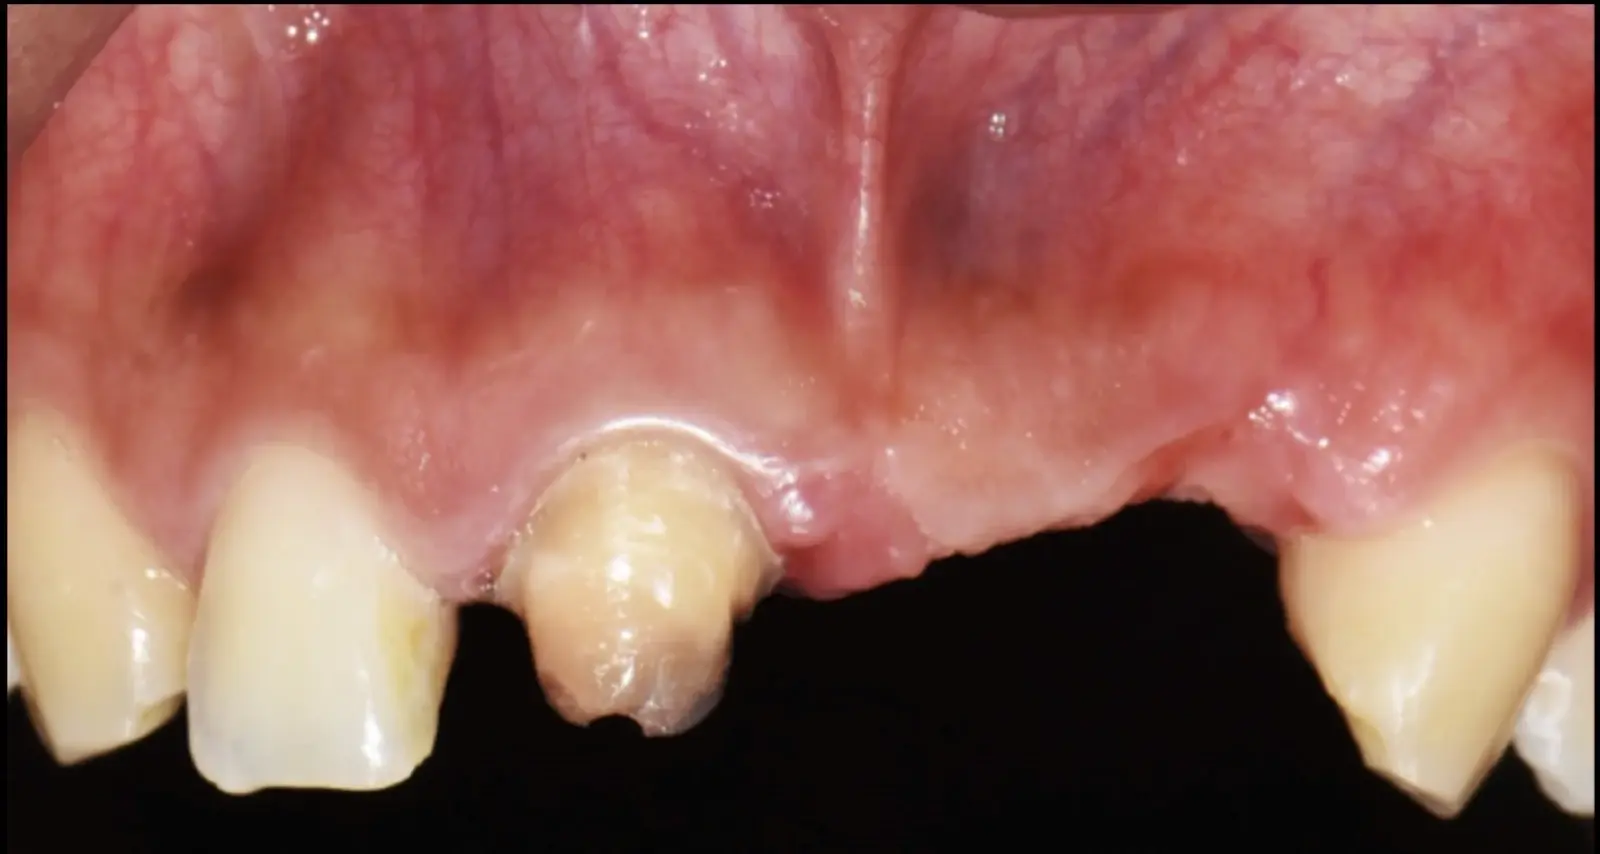

Figura 46. Control a los 10 días post cirugía.